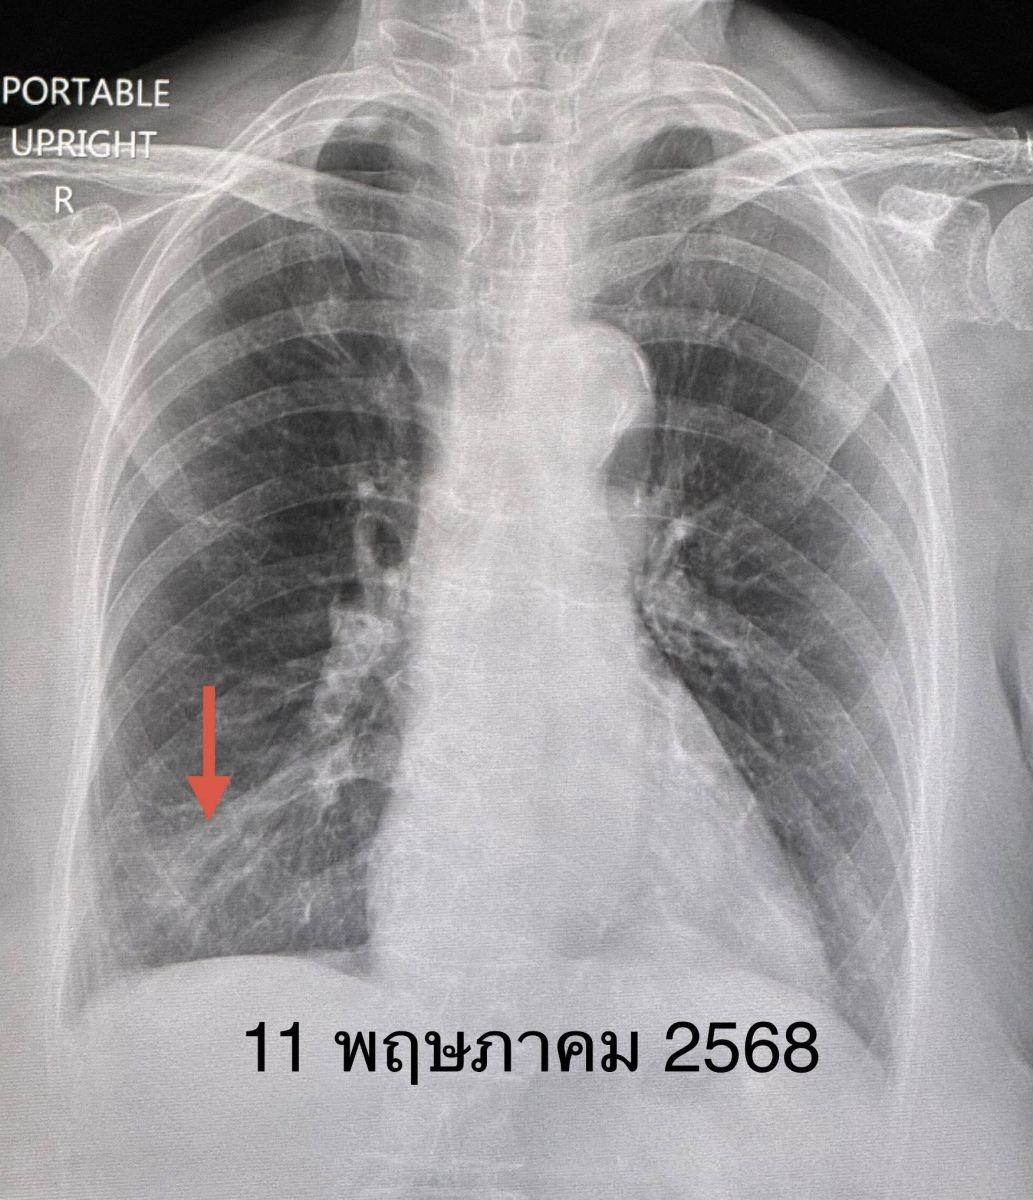

วันที่ 19 พฤษภาคม 2568 นพ.มนูญ ลีเชวงวงศ์ แพทย์ทางด้านโรคระบบทางเดินหายใจ โพสต์เฟสบุ๊ก ระบุ ผู้ป่วยหญิงอายุ 86 ปี มีไข้สูง ปวดตัว ไอเล็กน้อย มีน้ำมูก เจ็บคอ 1 วัน ไม่เหนื่อย ไม่เคยติดโควิด เคยฉีดวัคซีนป้องกันโควิด 4 เข็ม ปกติแข็งแรงดี เป็นโรคความดัน ไขมันสูง เข้านอนโรงพยาบาลวันที่ 11 พฤษภาคม 2568 ตรวจร่างกาย อุณหภูมิ 39 องศาเซลเซียส ระดับออกซิเจนที่ปลายนิ้ว 95% ฟังปอดปกติ เอกซเรย์ปอดเห็นฝ้าขาวเล็กน้อยที่ปอดข้างขวาด้านล่าง (ดูรูป) แยงจมูกตรวจพบเชื้อไวรัสโควิด-19 ไม่พบไวรัสทางเดินหายใจตัวอื่น

วินิจฉัย : ปอดอักเสบเล็กน้อยจากโรคโควิด-19 ให้ยาต้านไวรัส เรมเดซิเวียร์ (Remdesivir) ฉีดเข้าทางหลอดเลือดดำ ไข้สูงลอย 3 วันแรก หลังได้ยาเรมเดซิเวียร์ 3 วัน ไข้เริ่มลงและเอกซเรย์ปอดเริ่มดีขึ้น ให้ยาฉีดต่อจนครบ 5 วัน ไม่มีไข้ ไอดีขึ้นมาก เอกซเรย์ปอดอักเสบหายเป็นปกติ (ดูรูป) กลับบ้านได้ในเวลา 5 วัน